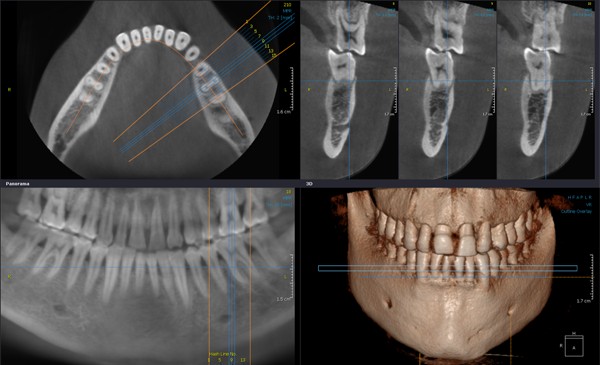

К счастью, в современной стоматологической диагностике, и в нашей клинике в частности, используются специализированные дентальные томографы. Это оборудование не только позволяет получать высокоточные снимки с толщиной среза 0,15-0,3мм, но и создавать 3D-модель сканируемой области. Имея такую информацию, стоматолог получает возможность изучить необходимый участок зубочелюстной системы под любым углом и с любой точки зрения и правильно составить дальнейший план лечения. Программа точно воссоздает все необходимые данные: форму, расположение, строение и размеры элементов челюстно-лицевой области.

Также, что немаловажно: сканирование происходит в течение 10-15 секунд, проводится в удобном для пациента положении, а получаемое облучение при таком исследовании незначительно – в семь-десять раз меньше чем при традиционной томографии.